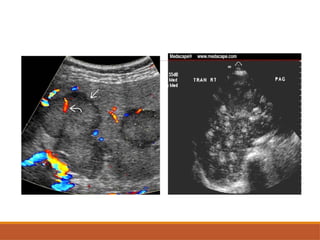

• #18 Grey scale usg image showing a well defined isodense mass in segment 7 of right lobe on doppler interrogation there is a stellate pattern of blood vessel arrangement

• #19 Axail cect image of focal nodular hyperplasia in arterial and portal venous phase showing arterially hypervascular mass with a central non-enhanced scar in segment V of the liver which isodense with surrounding hepatic parenchyma on the portal venous and delayed phases.

USG

Subtle iso-echoic mass with contour abnormality.

Displacement of vascular structure.

Central scar- hypo-echoic linear or stellate

area, may be hyper-echoic.

Doppler study: well developed peripheral & central blood

vessels are seen.